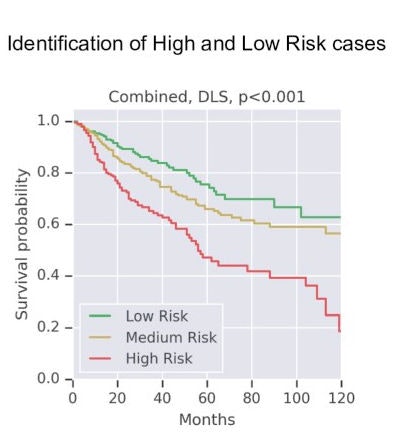

Training for the system involved 9,086 digitized whole-slide images from 3,664 cases. Testing encompassed 3,009 digitized images from 1,216 cases. Overall, the deep-learning system scoring was significantly associated with disease-specific survival, Google computer scientist Ellery Wulczyn and colleagues reported, noting a hazard ratio of 1.58.

Drilling down to performance by tumor type, the system was associated with significant prediction of survival in five of the 10 cancers studied (p = 0.0002 to p = 0.0257). It was also possible to stratify risk within some cancer stages (II and III).

"Our analysis demonstrates the potential for this approach to provide significant prognostic information in multiple cancer types, and even within specific pathologic stages," Wulczyn and colleagues wrote.

Consequently, they reported wide confidence intervals in the performance results and view the data as supporting proof-of-concept but needing a lot more work.